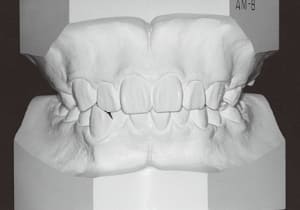

25 After Phase 2 Treatment 6-6-’94

26 After Retention 7-8-’96

30 After Phase 2 Treatment 6-6-’94

31 After Retention 7-8-’96

The facial type changed from backward divergent to straight between the initial visit and after retention (27–31). Cephalometric X-rays reveal significant mandibular growth (32).

Treatment period from initiation to completion of active treatment lasted 6 years and 2 months, with appliances worn for 3 years and 8 months of that time. Retention lasted 2 years and 2 months following active treatment.